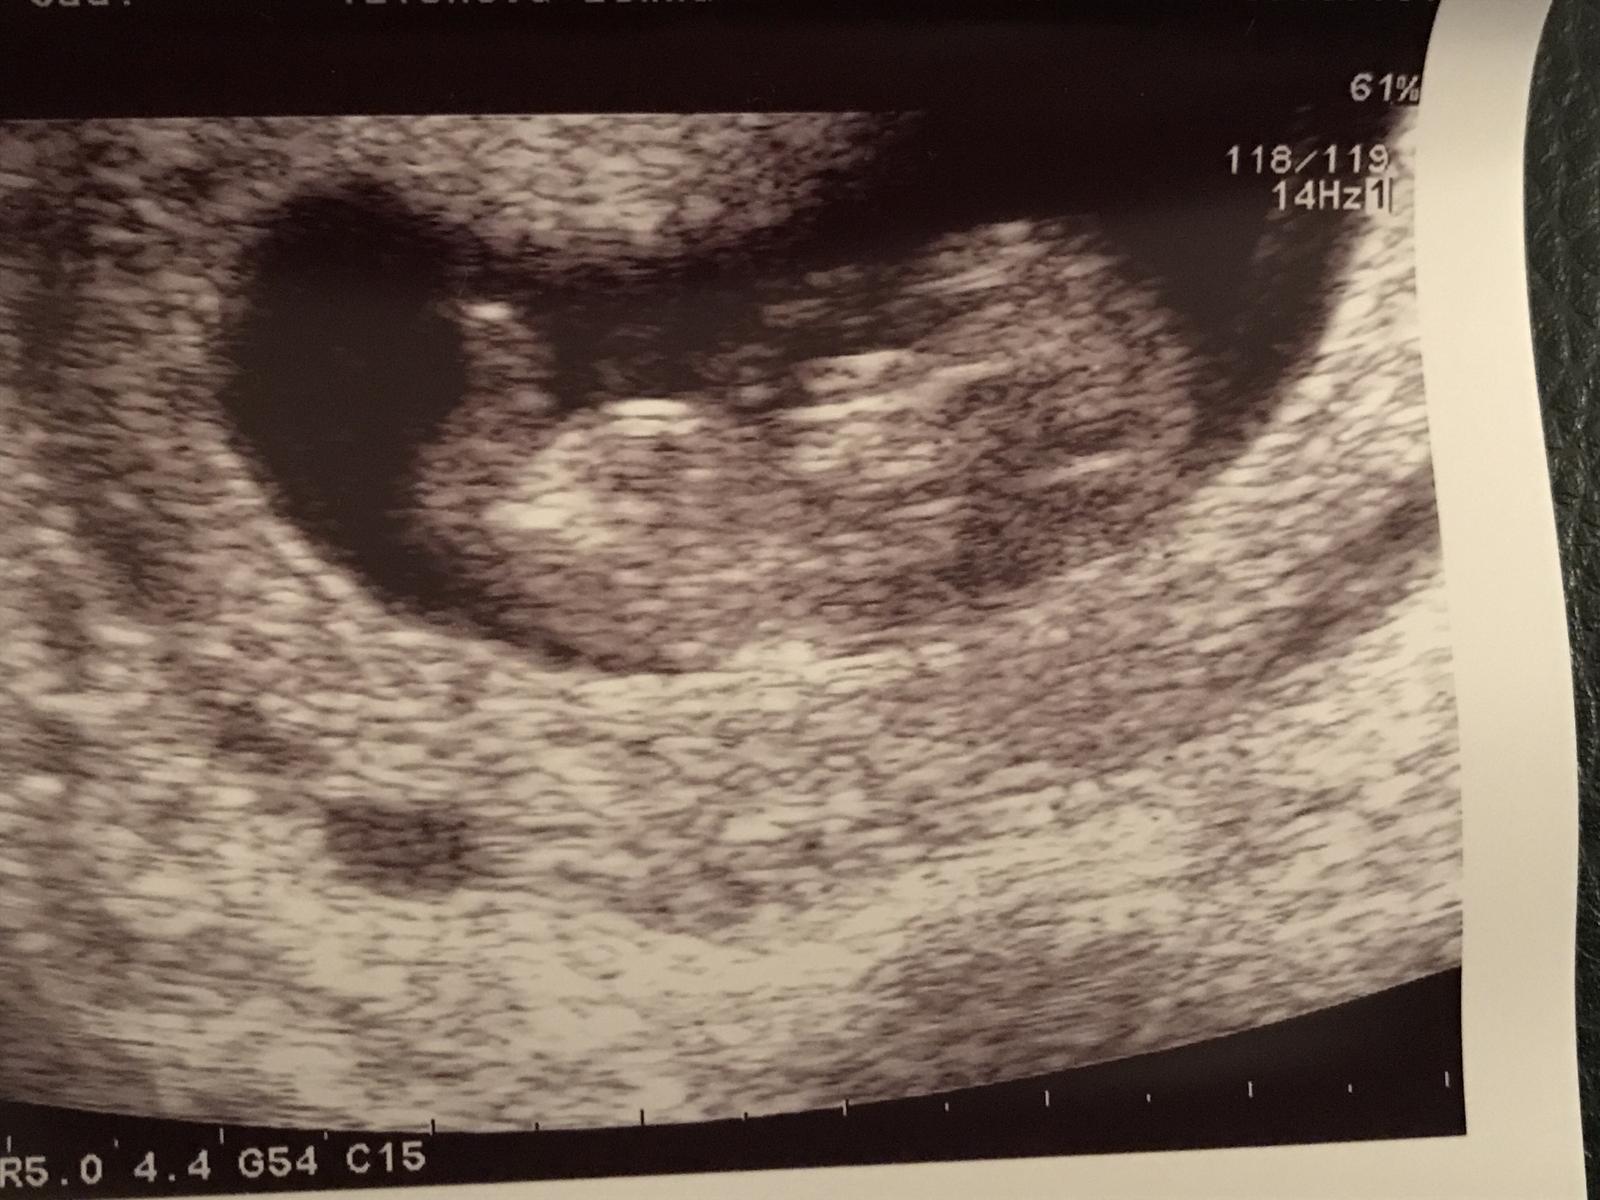

Tak hlasim 1.dc po 30 dnech.,tak zase znovu,ale je to vlastne prvni samovolna ms po 3 mes,tak jsem rada,ze je vse o.k.

A neboj, bude to dobre 🙂 v pátek mas screening už?